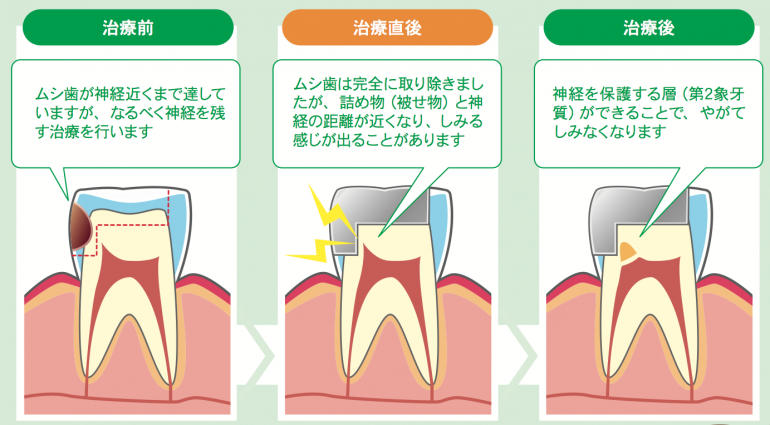

Q;虫歯治療したのに痛いのはなんでですか?

A;治療後に痛みが出るのは、治療した患部と内部の神経との距離が近くなっているからです。

虫歯になっても神経まで到達しないと痛みは出ません

なぜなら歯の表面は痛みを感じないからです

神経が痛みを感じます

虫歯治療後の痛みが起こるのは、削った範囲と神経との距離が近くなり、外からの刺激でしみたり痛みが出るためです。

これは神経を取らずに歯の延命処置をしているため、申し訳ないですが、症状が出ることがあります。

治療したにも関わらず痛みが出る場合は、

もしそのまま治療しなければ、内部で無症状で虫歯が進行し確実に神経を取っていたということになります

虫歯が深く神経との距離が近かったにも関わらず痛みが全く出ない場合もあります

この違いは、人により歯の痛みを感じる敏感さが違うと考えています

そのため、同じような虫歯の深いところを治療をしても右と左で症状が違う時もあります

治療してから数ヶ月経って症状が出ることもあります

治療後の痛みが出るかどうか、痛み方の具合は予測はできないのが現状です

そのため、治療後にしみることや痛みが出ることがあると説明をさせて頂いています

Q;治療後にしみることがあった場合は治るの?

A;徐々に回復してくることがあります

治療後は、神経を保護する第2象牙質ができやがてしみなくなります

歯は、詰め物と神経の距離を少しでも遠くするために神経を保護する層(第2象牙質)を作り始めます。

この第2象牙質が完全に感染するまでに6ヶ月ほどかかると言われています

歯の内部の修復は石灰化をするため時間がかかります

第2象牙質ができて内部が修復される前に、痛みが出てしまったりしみる症状が強い場合は残念ながら神経を取る必要があります

ほとんどの人が治療したら痛みがなくなるものだと思っていらっしゃいますが、残念ながら痛みが出てしまうほどの虫歯があったと思って下さい

治療したにも関わらず痛みが出る場合は、もしそのまま治療しなければ、内部で無症状で虫歯が進行し確実に神経を取っていたということになります